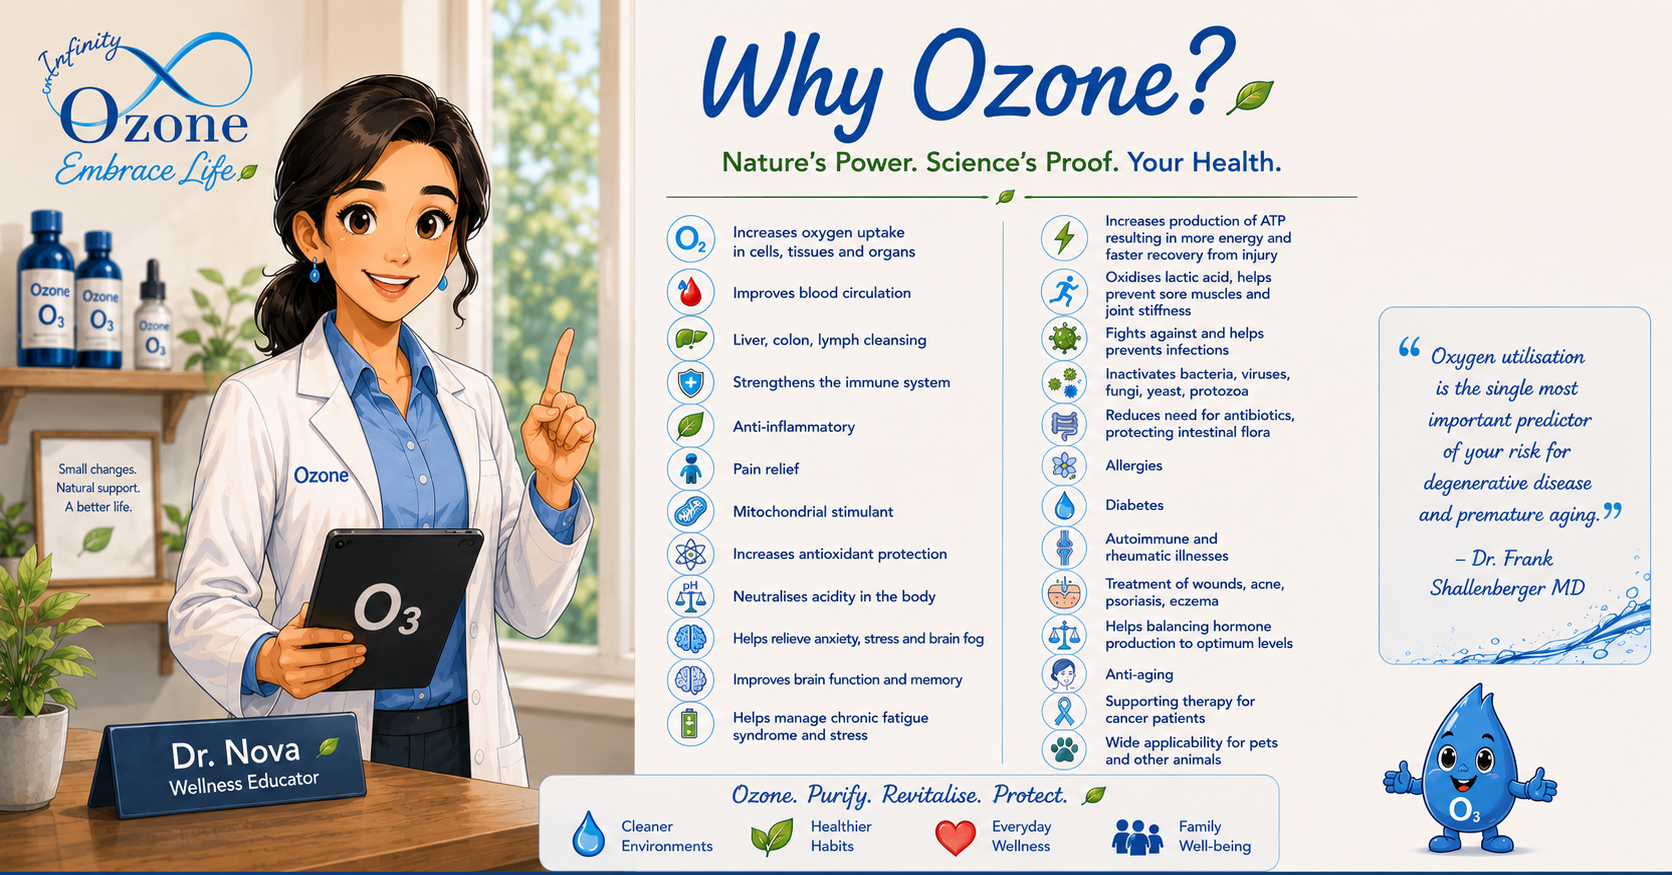

Science-Backed, Spirit-Led

Our methods are rooted in scientific research and guided by holistic values. From oxygenation and detox to spiritual wellness, our approach supports you in achieving full-body health with integrity and care.